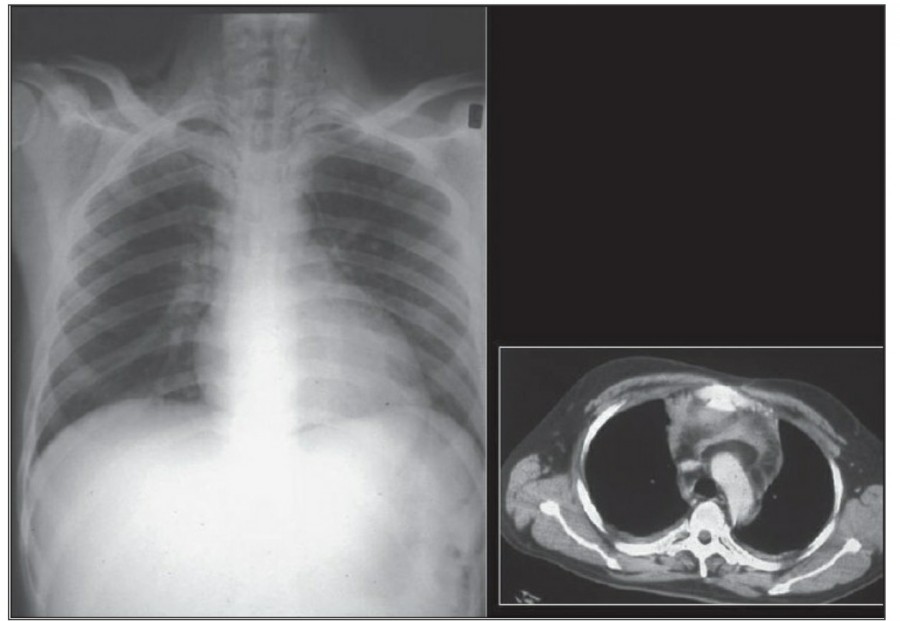

Pleural effusion

방사선 소견상 Pleural effusion은 환자 흉부의 dependent area에 고인다. Erect position에서 확인하기가 쉬운데, 폐의 base에 고임으로써 costophrenic angle blunting을 보이고 lower lobe vessel들의 흐리게 한다. Supine position에서는 확인이 더 어려운데, pleural fluid는 posterior basilar space에 고여서 폐 base 쪽으로 intensity가 증가하는 homogenous density를 보인다. 정상적인 bronchoalveolar marking은 이와 같은 veil-like density 안에서 확인 가능하다. Fluid 양이 늘어나면서 diaphragm의 윤곽이 흐릿해지고 costophrenic angle도 없어지는데, 이 costophrenic angle blunting이 없더라도 pleural space에 1L 정도의 pleural fluid가 있을 수 있다는 것을 기억해야 한다. 그 양이 더욱 늘어날 수록 fluid는 lung의 apex에서 pleural cap으로 나타날 수 있으며, 이는 supine position에서도 확인 가능하다. Pleural fluid는 lung의 medial side에 고일 수도 있으며 이는 mediastinum의 확장으로 보일 수도 있다.

적은 양의 pleural fluid는 꼼꼼히 확인하더라도 supine radiograph에서 놓칠 수 있는데, 만약 chest X ray에서 보이지 않지만 임상적으로 의심이 되는 경우에는 lateral decubitus film으로 확인해 볼 수 있다. Fluid는 dependent position에 고이므로 환자를 의심되는 방향으로 옆으로 눕혀야 한다. Lateral decubitus film은 적은 양의 pleural fluiid는 물론이고 loculated effusion과 free effusion을 확진하는 데도 도움이 된다. 특히 loculated effusion은 한 개 이상의 drain이 필요할 수 있으므로 pleural drainage를 고려할 때 특히 중요한 검사이다. 중환자에서 흔하게 나타나는 subplumonic effusion은 lung base에 존재하는 pleural effusion을 말하는데, chest X ray 상에서 raised hemidiaphragm with flattening and lateral displacement of the dome 형태로 나타나며, lateral decubitus film이 도움이 된다.

Loculated pleural effusion의 진단은 쉽지 않은데, 특히 fissure 안에 있을 때 어렵다. Loculted effusion이 minor fissure 안에 있고 right middle lobe atelectasis가 있다면 supine chest radiograph에서 감별이 어려운데, interlobular effusion은 biconvex edges와 homogenous density로 나타나고 minor fissure는 유지되는 반면, atelectasis는 concave margin과 inhomogenous density로 나타나며 right heart border와 minor fissure가 보이지 않게 된다. 이런 경우 erect lateral radiograph나 CT가 도움이 될 수 있다.